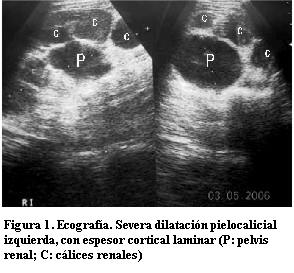

Se solicitó una ecografía abdominal que mostró el riñón izquierdo aumentado de tamaño, a expensas de una severa dilatación pielocalicial midiendo la pelvis renal 50 mm en sentido antero posterior; el espesor del parénquima mide 3 mm, sin diferenciación córticomedular. Uréter homolateral dilatado, tortuoso, de 30 mm de calibre en toda su extensión; en el sector pelviano su interior contiene nivel líquido-líquido, con material heterogéneo, ecogénico en su porción declive. No se logra visualizar la entrada del uréter en la vejiga. Riñón derecho sin alteraciones topográficas, morfológicas ni ecoestructurales. Vejiga sin alteraciones parietales ni del contenido. No se observa líquido libre en la cavidad peritoneal. Resto de la ecografía abdóminopelviana sin alteraciones. En suma: cuadro clínico imagenológico compatible con uréterohidronefrosis infectada (figuras 1 y 2).